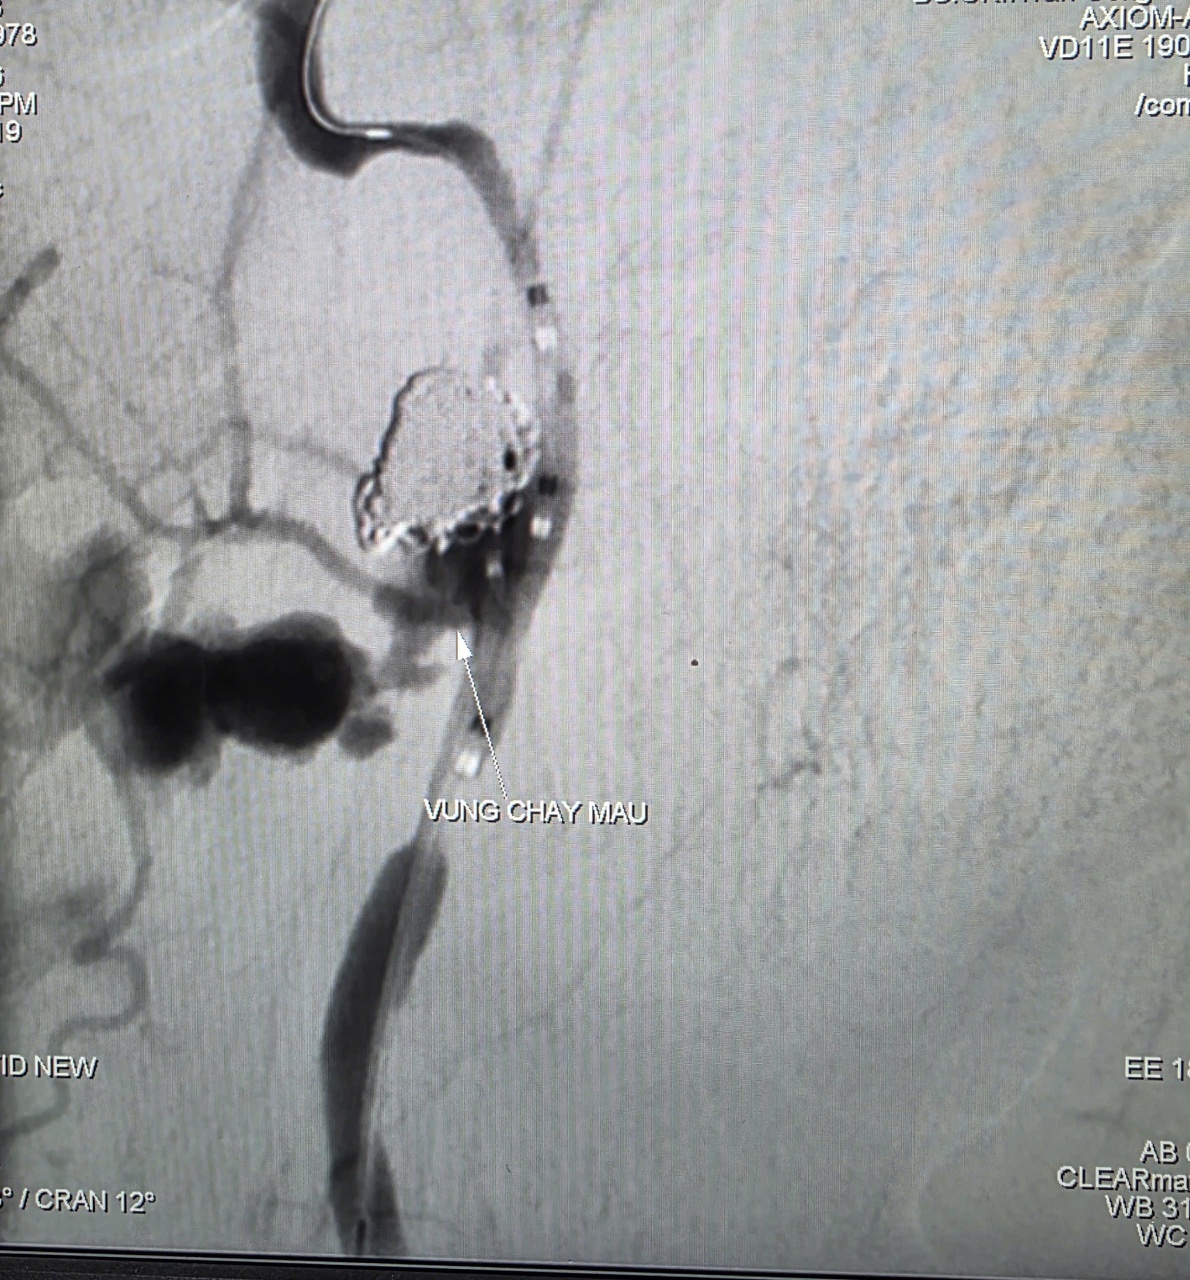

Kết quả cho thấy khối u vùng hầu lệch phải xâm lấn động mạch cảnh trong, xuất hiện ổ giả phình động mạch cảnh trong dưới nền sọ kèm dấu hiệu thoát thuốc cản quang, nguy cơ xuất huyết ồ ạt đe dọa tính mạng.

Trước tình huống nguy kịch, các bác sĩ quyết định thực hiện chụp và can thiệp cầm máu bằng hệ thống chụp mạch số hóa xóa nền (DSA). Thủ thuật do BS.CKII Trần Công Khánh, Phó Trưởng khoa Chẩn đoán hình ảnh cùng ê-kíp thực hiện.

Kết quả chụp mạch ghi nhận ổ giả phình động mạch cảnh trong phải đoạn cổ, kích thước 4,2 x 4,8 mm, cổ túi phình rộng và đang chảy máu. Ê-kíp đã sử dụng bóng chẹn dòng chảy, sau đó đưa vi ống thông đến vị trí tổn thương và thả 9 vòng xoắn kim loại (coils) gây tắc hoàn toàn túi phình và động mạch cảnh trong phải nhằm kiểm soát nguồn chảy máu.